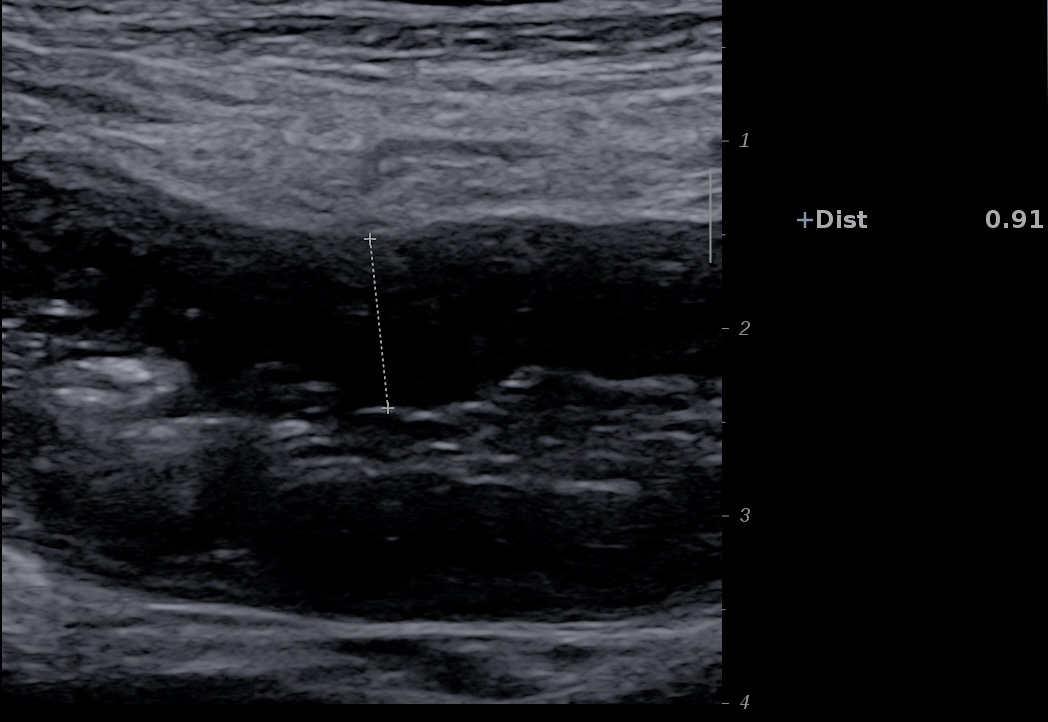

Ci dessous RCH avec sous muqueuse épaisse et hyperéchogène.

Ci-dessous seule la sous muqueuse hyperéchogène est épaissie